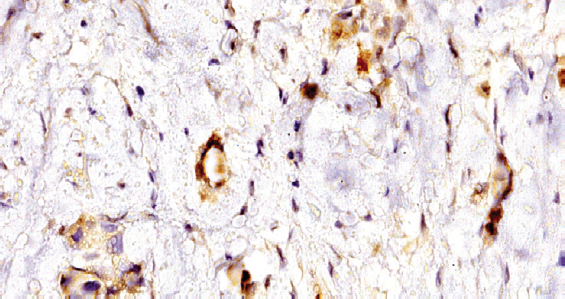

При иммуногистохимическом исследовании материала обнаружена достаточно распространенная экспрессия anti-BLV в различных структурах ткани РМЖ (рис. 1). Продукт реакции определялся в виде зерен и глыбок на поверхности клеточной мембраны, с преобладанием локализации в цитоплазме опухолевых клеток. Выявлена выраженная экспрессия данного вируса на стенке микрососудов (рис. 2). Обратило на себя внимание, что из четырех исследуемых групп экспрессия BLV наблюдалась только в случаях тройного негативного РМЖ (табл. 1).

Рис. 2. Рак молочной железы. Экспрессия антигена вируса лейкоза коров в микрососудах и опухолевых клетках, увеличение в 600 раз; иммуногистохимическая окраска

Fig. 2. Expression of cow leukosis virus antigen in breast cancer tissue, zoom in 600; immunohistochemical staining

Авторы впервые в мире использовали иммуногистохимический метод детекции антигена вируса BLV, который позволил достоверно подтвердить его присутствие в опухолях молочной железы со схожими молекулярно-генетическими и иммуногистохимическими профилями. Выявленная экспрессия антигена вируса на стенке микрососудов представляет значимый факт для оценки понимания взаимосвязи развития РМЖ и вируса лейкоза коров.